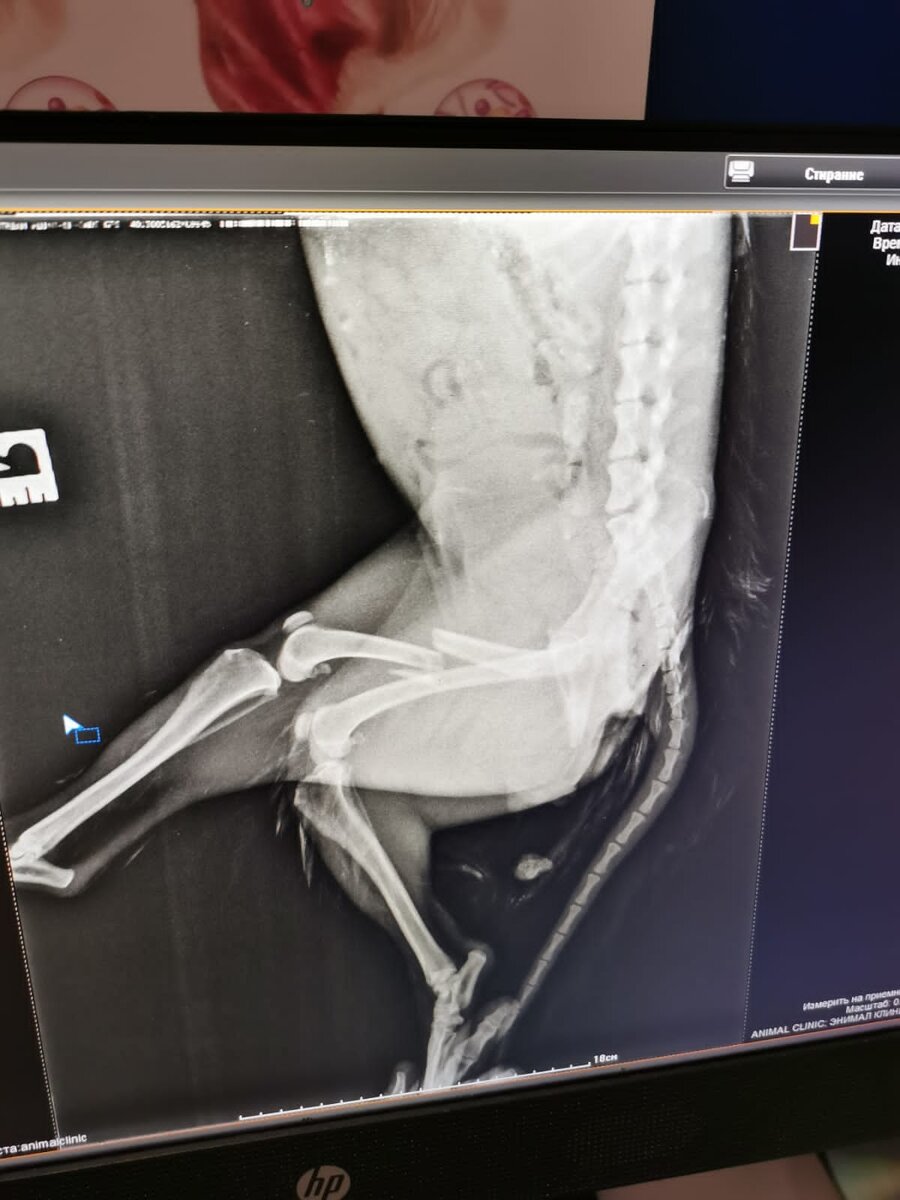

Сейчас она в клинике , операция назначена на завтра !

Точную сумму к сбору не знаю ,уже почти 8 потрачено ,операция и стационар в итоге сколько выйдут ,исходя из опыта,могу предполагать только. что чуть больше 15 тыс …